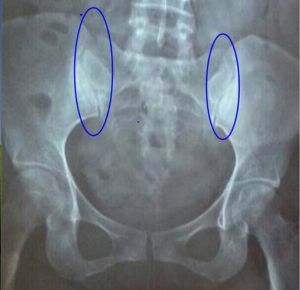

骶髂關節由凸凹不平相互交錯的耳形關節面組成,前後有長短不等的韌帶予以穩定,軀幹的重力經骶髂關節傳達至兩下腰。

當孕婦受內分泌改變的影響,或因長期臥床,腰麻或全麻後均能引起骶髂關節鬆弛,影響骶髂關節的穩定,當受到外力時引起骶髂關節扭傷或錯位。但由於骶髂關節堅強而穩定,不易引起扭傷或錯位。當姿勢不正、肌力失調、韌帶鬆弛時,扭轉的外力可使凸凹不平的骶髂關節面排列紊亂,間隙加寬。在關節腔負壓的情況下將滑膜吸入關節間隙嵌頓,引起劇烈疼痛。根據扭傷的方向不同可引起骶髂關節前脫位或後脫位。

(一)骶髂關節前脫位 是當髖關節伸直,膝關節屈曲,拉緊股四頭肌和髂股韌帶向前牽拉髂骨時,軀幹、脊柱及骶骨,向後旋轉的外力可使髂骨向前移位。

(二)骶髂關節後脫位 當髖關節屈曲,膝關節伸直,膕繩肌緊張向後牽拉髂骨時,軀幹脊柱及骶骨向對側前方旋轉時,則骶骨與髂骨發生方向相反的扭轉,可引起髂骨後旋移位。